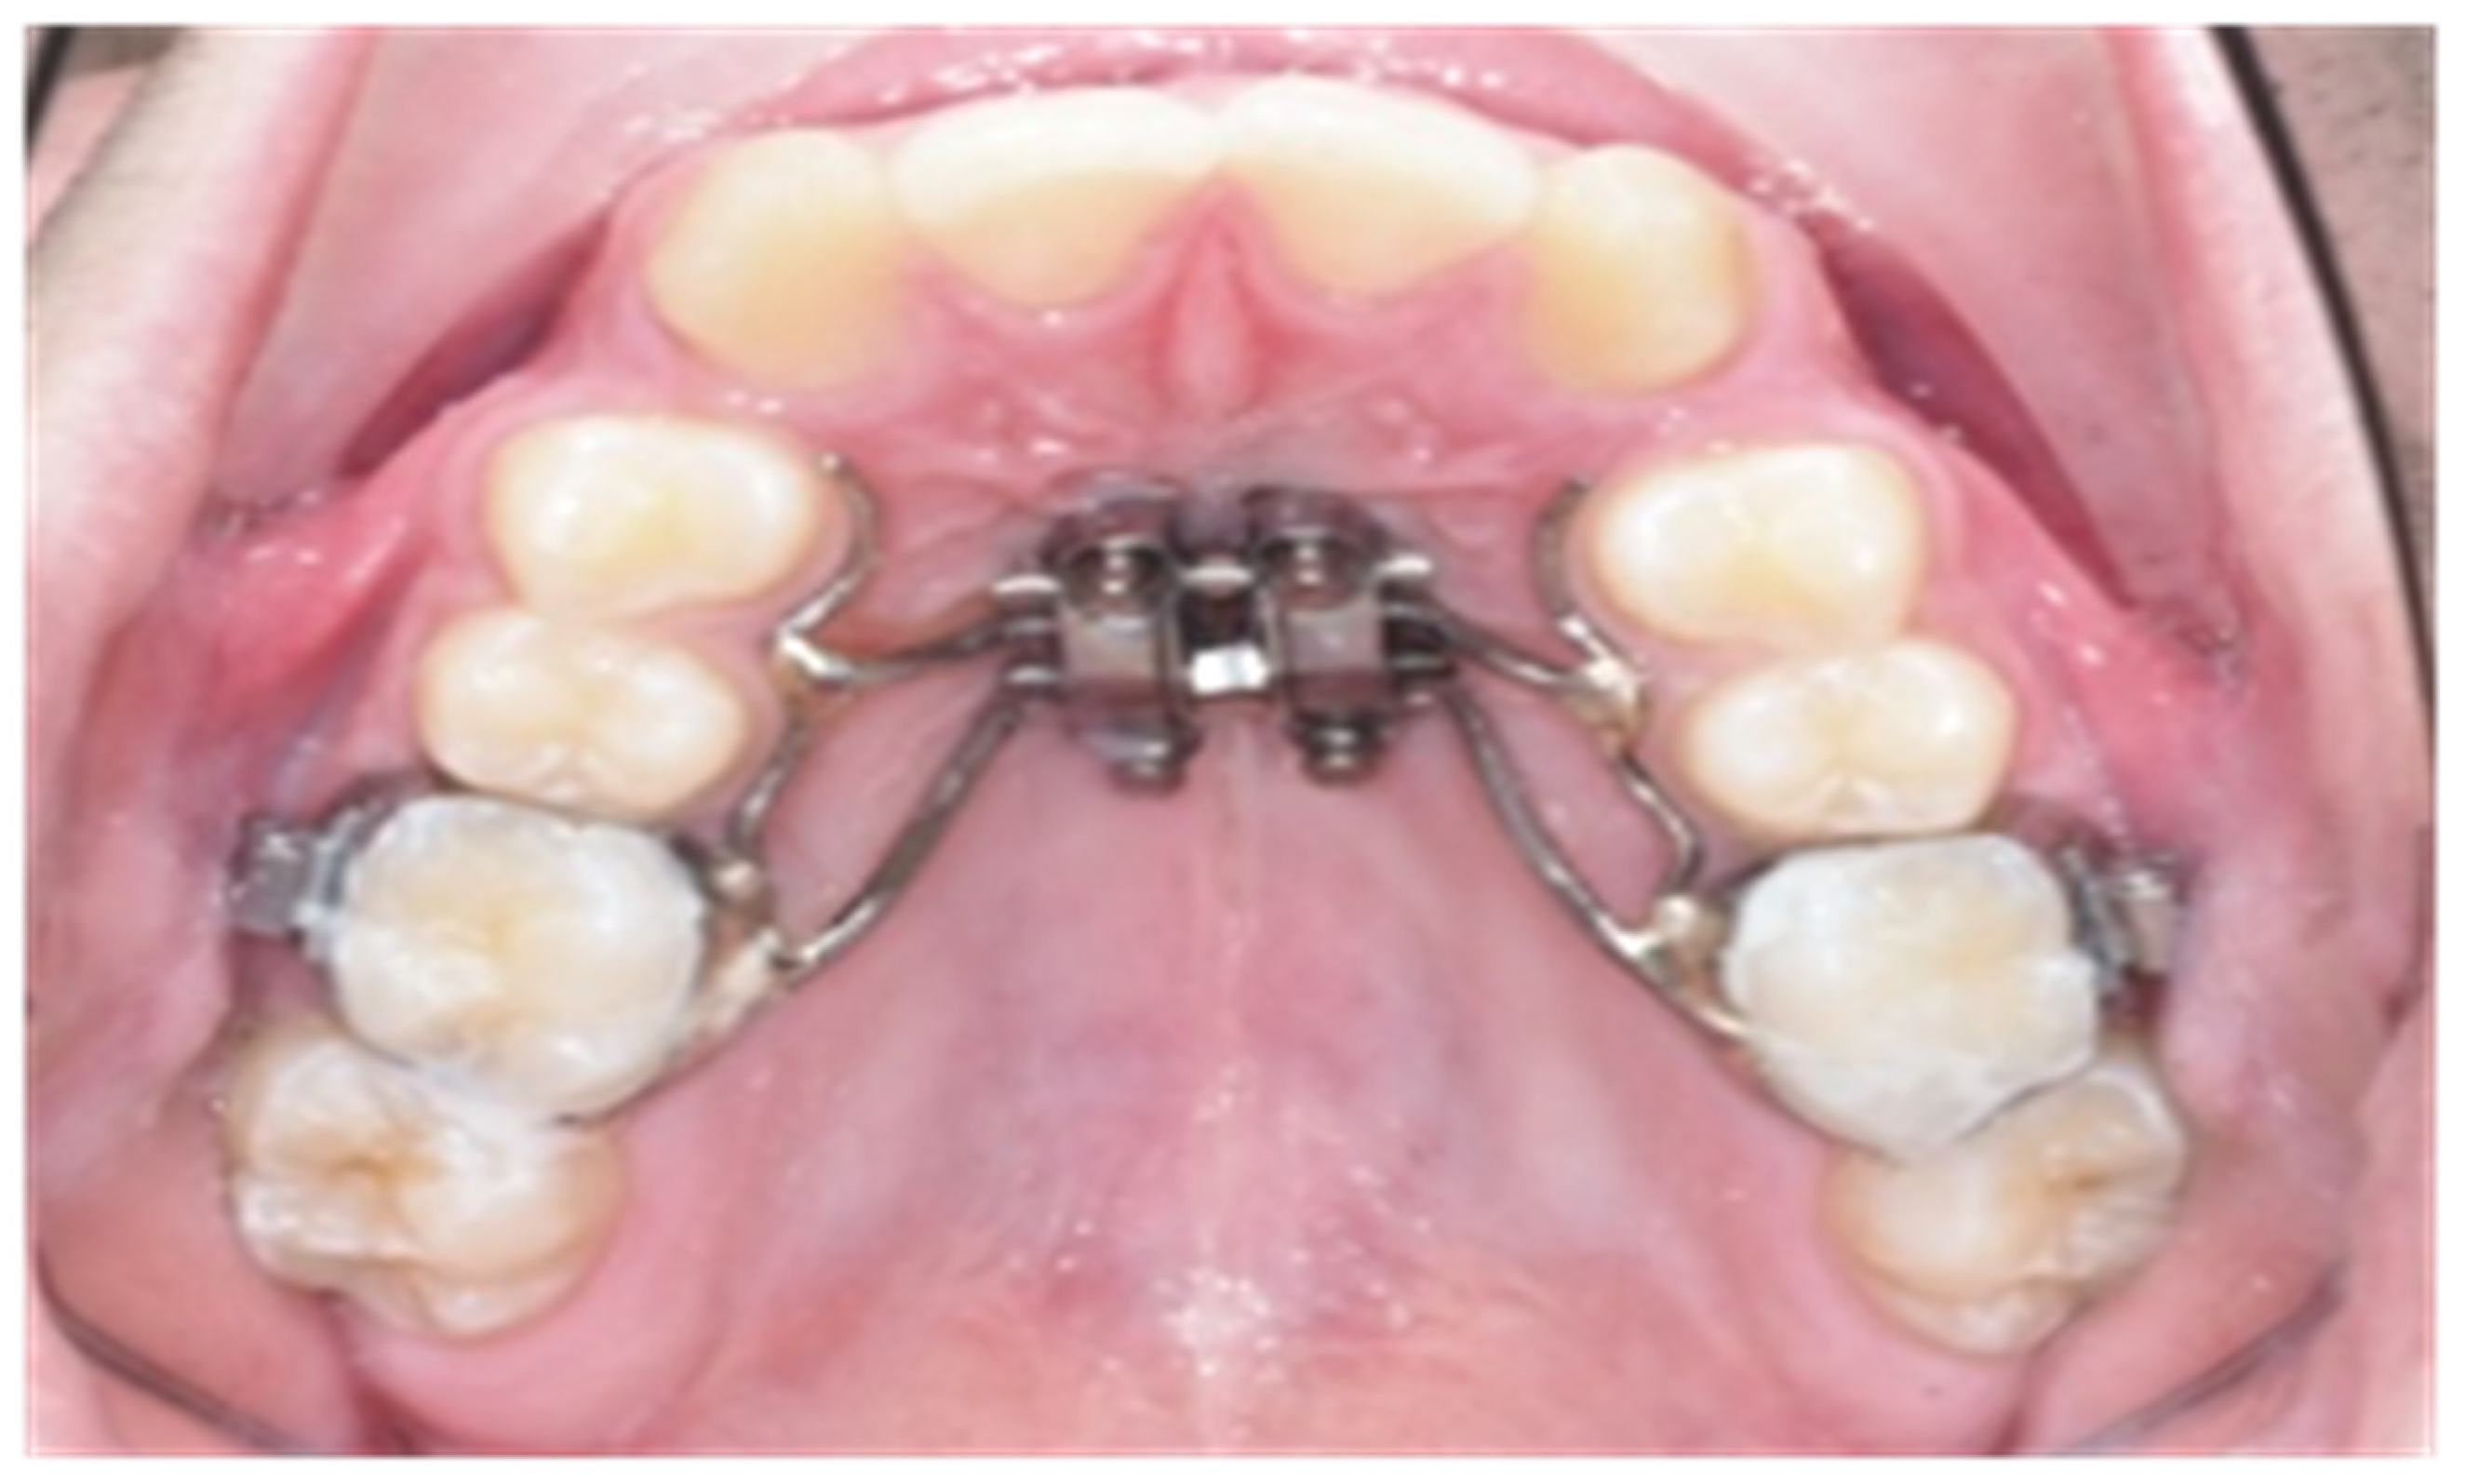

2. Material and Methods